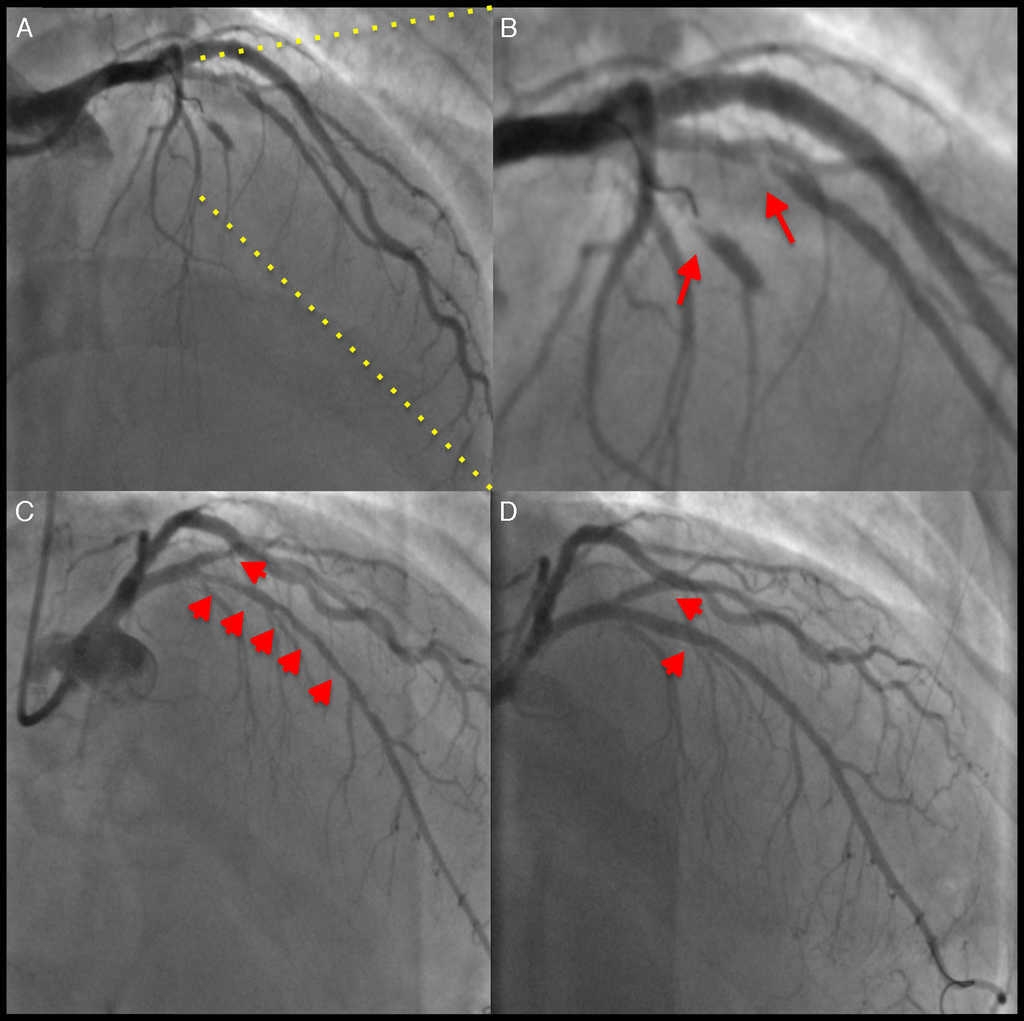

Presentamos el caso de un paciente varón de 57 años con antecedentes médicos de hipertensión arterial sistémica y que se presentó en nuestro servicio con historia de angina crónica estable. Se le realizó estudio de perfusión miocárdica con esfuerzo físico que objetivó dolor de tipo anginoso durante la prueba, y en las imágenes de medicina nuclear, isquemia miocárdica grave en la pared anterolateral. Se le realizó estudio de coronariografía diagnóstica que objetivó oclusión total crónica de la arteria descendente anterior (DA) posterior al nacimiento del primer ramo diagonal, mismo que tenía estenosis severa en su segmento proximal (fig. 1. A y B). Se preparó la lesión de la DA, predilatando con 2 balones compliantes de 1.50 × 20 mm y 2.50 × 20 mm hasta 16 atmosferas y el ramo diagonal se predilató con balón compliante de 2 × 15 mm a 12 atmosferas (fig. 1. C). En el ramo diagonal se implantó stent de cromo-cobalto y liberador de everolimus de 2.50 × 16 mm a 12 atmosferas. La lesión larga de la DA se trató con 3 DVB (Absorb, Abbott Vascular, Santa Clara, California, EE. UU.) de distal a proximal de 2.50 × 18 mm, 3 × 28 mm y 3.50 × 18 mm a 8 atmosferas, solapados mediante las guías de platino de los dispositivos. Se realizó optimización a la DA con balón no compliante de 3 × 20 mm hasta 14 atmosferas, de distal a proximal (fig. 1. D). Finalmente se realizó estudio de tomografía de coherencia óptica intracoronaria a la DA para corroborar el adecuado posicionamiento de los 3 DVB, así como la zona de solapamiento que fue de 2 mm tanto en el distal-medio como en el medio-proximal (fig. 2).

Figura 1 A) Imagen angiográfica donde se objetiva la oclusión total crónica de la descendente anterior desde su segmento medio y la estenosis crítica del ramo diagonal proximal. B) Imagen en aumento donde se objetivan ambas estenosis (flechas rojas). C) Imagen angiográfica posterior a la angioplastia con balón de ambas estenosis (flechas rojas). D) Resultado angiográfico final posterior a la implantación en el ramo diagonal del stent de cromo-cobalto liberador de everolimus y del solapamiento de 3 DVB en la descendente anterior (flechas rojas).